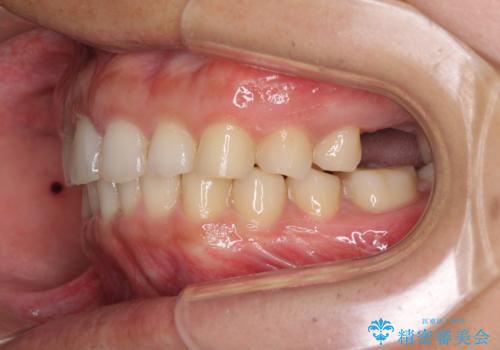

- 深い咬み合わせと前歯のデコボコ、奥歯の欠損を気にして来院された患者様です。

歯列矯正はインビザラインを使用し、矯正治療中の適切な時期に奥歯の欠損部位にインプラントを埋入することとしました。